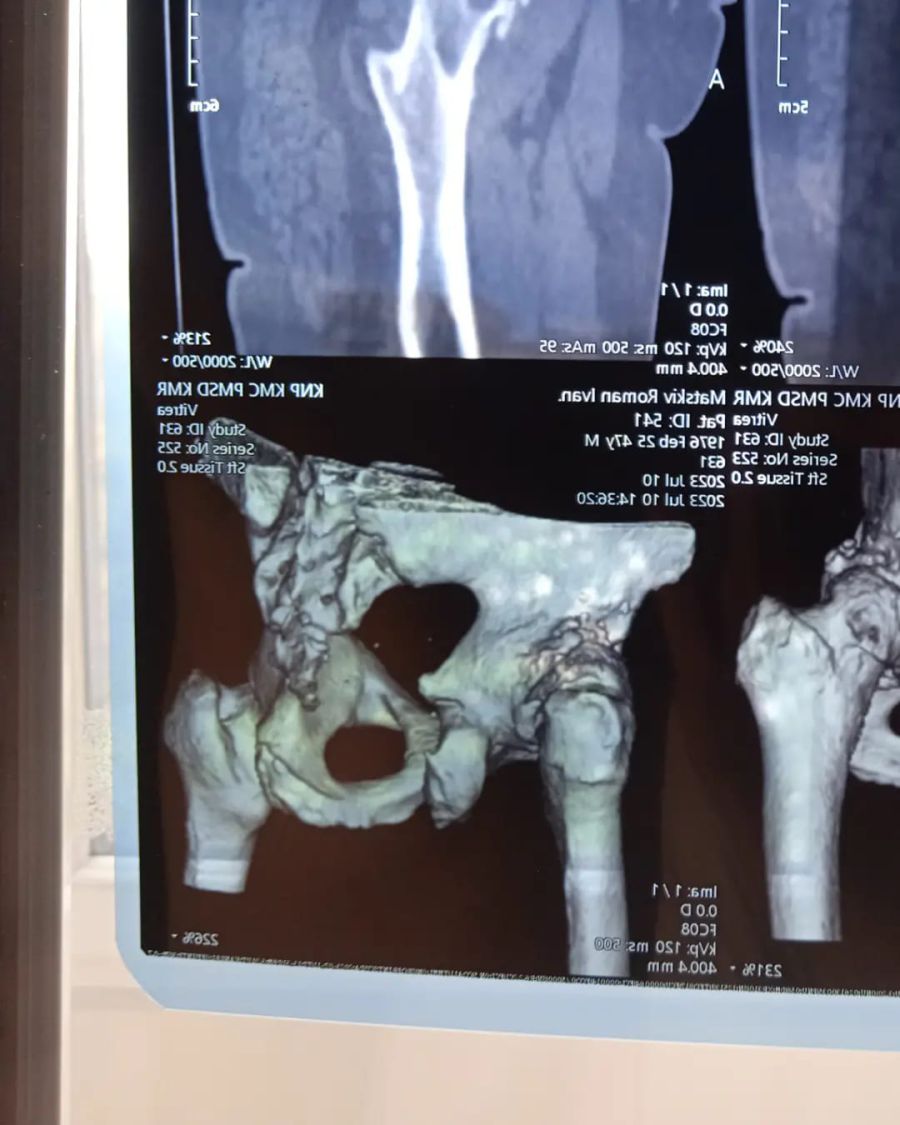

"В нашій сім'ї сталася прикра ситуація. В мого батька, Мацьків Романа, діагностувати лівобічний коксартроз IV стадії та правобічний коксартроз II стадії. Це дегенеративно-дистрофічне захворювання, при якому руйнуються хрящі, що покривають поверхню голівки стегна і вертлюжної западини. Ліва нога стала коротша на 3 сантиметра", — йдеться в повідомленні.

"Лікар сказав, що праву ногу ще можливо лікувати, і в цьому є сенс. А от ліва нога потребує ендопротезування і ,бажано, якнайшвидше, поки захворювання не почало ще більше прогресувати на правій нозі", — розповіла дочка.